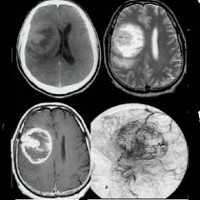

Глиома головного мозга — наиболее распространенная опухоль головного мозга, берущая свое начало из различных клеток глии. Клинические проявления глиомы зависят от ее расположения и могут включать головную боль, тошноту, вестибулярную атаксию, расстройство зрения, парезы и параличи, дизартрию, нарушения чувствительности, судорожные приступы и пр. Глиома головного мозга диагностируется по результатам МРТ головного мозга и морфологического исследования опухолевых тканей. Вспомогательное значение имеет проведение Эхо-ЭГ, ЭЭГ, ангиографии сосудов головного мозга, ЭЭГ, офтальмоскопии, исследования цереброспинальной жидкости, ПЭТ и сцинтиграфии. Общепринятыми способами лечения в отношении глиомы головного мозга являются хирургическое удаление, лучевая терапия, стереотаксическая радиохирургия и химиотерапия.

Глиома головного мозга встречается в 60% случаев опухолей головного мозга. Название «глиома» связано с тем, что опухоль развивается из глиальной ткани, окружающей нейроны головного мозга и обеспечивающей их нормальное функционирование. Глиома головного мозга представляет собой в основном первичную внутримозговую опухоль полушарий мозга. Она имеет вид розоватого, серовато-белого, реже темно-красного узла с нечеткими очертаниями. Глиома головного мозга может локализоваться в стенке желудочка мозга или в области хиазмы (глиома хиазмы). В более редких случаях глиома располагается в нервных стволах (например, глиома зрительного нерва). Прорастание глиомы головного мозга в мозговые оболочки или кости черепа наблюдается лишь в исключительных случаях.